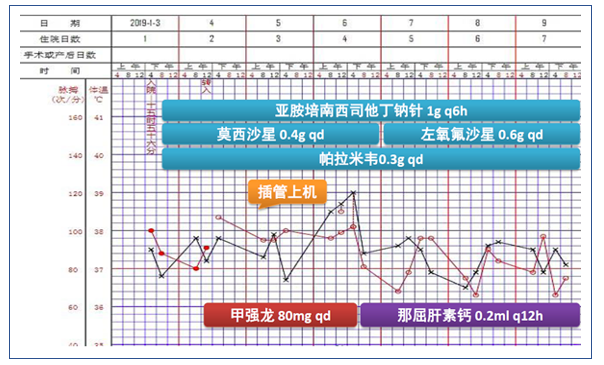

病情发展

图3 患者初始治疗方案及生命体征变化情况